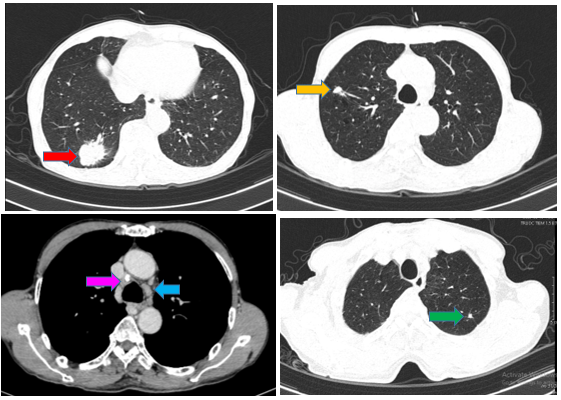

- Cắt lớp vi tính lồng ngực tháng 10/2024 (trước điều trị)

Hình 1:

Hình ảnh chụp CT ngực cho thấyPhổi phải phân thùy S10 có khối ~ 40x30mm bờ tua gai (mũi tên đỏ); thùy trên, thùy dưới còn lại có vài nốt đặc, lớn nhất đường kính 9mm (mũi tên màu cam); Phổi trái: thùy trên có nốt đặc đường kính 3m ngấm thuốc, bờ tua gai (mũi tên xanh lá cây). Nhiều hạch trung thất, lớn nhất ~ 16x12mm (mũi tên xanh dương), có hạch vôi hóa (mũi tên hồng)

+ Chụp CT ngực sau điều trị

Hình 4:

So sánh phim chụp cắt lớp vi tính lồng ngực trước điều trị kích thước khối u thùy dưới phổi phải từ 40x30mm (mũi tên đỏ) sau điều trị giảm còn 26x20mm (mũi tên vàng)

Hình 7: Hình ảnh các hạch trung thất trước điều trị lớn nhất ~16x12mm (mũi tên đỏ) giảm nhẹ sau điều trị còn 15x12mm (mũi tên vàng)